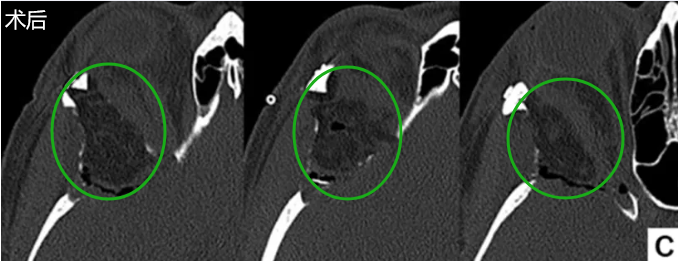

随后患者接受福教授主刀的眉弓切口手术及新月形眶缘颅骨切开术,最终实现全切,术后过程平稳,无并发症。术后第6天拆线,患者临床状况良好,疤痕几乎不可见,并且眼球突出有所消退。

结合眉部切口和新月形眶缘颅骨切开术,是对处理蝶骨嵴、前颅窝、中颅窝以及眼眶病变的经眶入路的简单、安全、有效改良。该技术融合传统内镜经眶入路和现代锁孔手术的优点。目前该技术不要求具备特定眼科手术技能,且可同时兼容显微镜和内镜使用,提高手术自由度和操作灵活性。